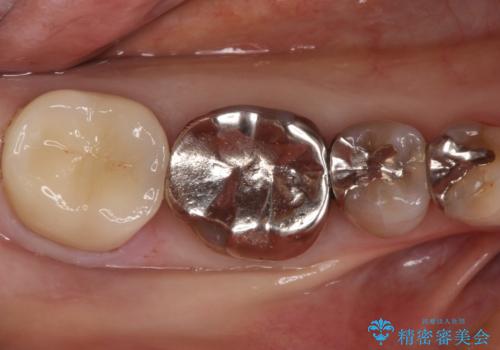

- 他院で入れたセラミックインレーがかけたことを主訴に来院されました。

他の部位にもむし歯を認めたため、優先度の高い歯から治療を行っております。

咬合力が強くかかる部分には欠けるリスクのほとんどない金属を用いることが最良ですが審美性に劣ります。

今回は白い材料での修復を希望されたため、欠けるリスクが高いセラミックインレーは避け、セラミッククラウンにて治療を行いました。